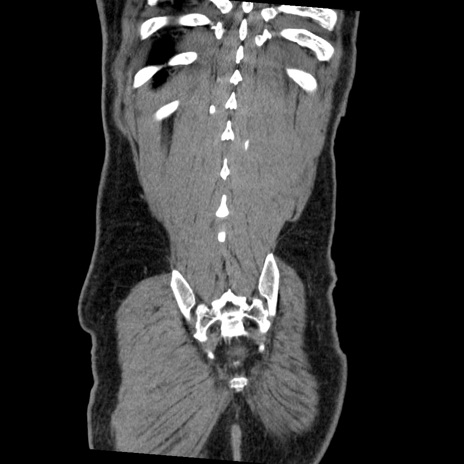

症例22(冠状断像)

【症例】50歳代男性

【主訴】腹痛

【現病歴】AVMからの被殻出血のため回復期リハ病棟入院中。 本日午後3時頃急に下腹部痛が出現した。

【既往歴】AVM、被殻出血、虫垂炎、高血圧

【身体所見】意識晴明、左半身不全麻痺、会話の理解は良好、36.5°C、腹部:膨隆、全体に板状硬、下腹部正中に圧痛点あり、反跳痛-、筋性防御不明、右下腹部にope scar

【データ】WBC 9400、CRP 0.06